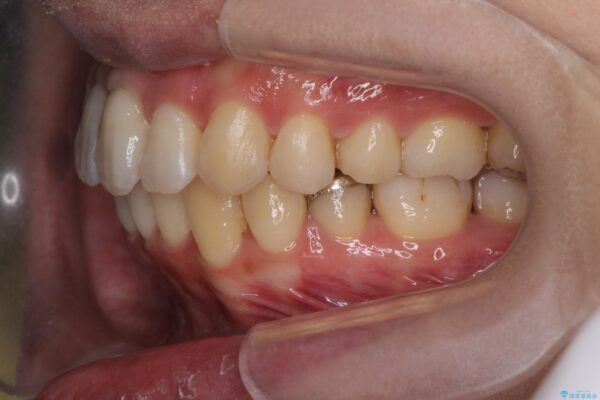

治療を終えて

患者様の協力度も高く、リファインメントなしで治療を終えることができました。

動的治療期間は約4か月となり、短い治療期間で前歯のガタつきが改善され大変喜んでいただけました。

治療後

気になる犬歯のガタつきをマウスピース矯正で改善 治療後画像 気になる犬歯のガタつきをマウスピース矯正で改善 治療後画像 気になる犬歯のガタつきをマウスピース矯正で改善 治療後画像 気になる犬歯のガタつきをマウスピース矯正で改善 治療後画像